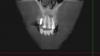

При прохождении КТ в 2011 г .была выявлена киста в области 21-21 зуба.

В 2003 году была проведена операция по резекции верхушки корней данных зубов, в 2008 году каналы зубов были заново перелечены и усилены металлическими штифтами. При наращивании коронковой части зубов 21-22 терапевт удлинил зубы вследствие чего на них увеличилась нагрузка и доставила дискомфорт.

post-23088-0-05077900-1320069184_thumb.jpg

post-23088-0-85945100-1320069186_thumb.jpg

post-23088-0-44942700-1320069187_thumb.jpg

post-23088-0-08601700-1320069188_thumb.jpg

post-23088-0-77081900-1320069268_thumb.jpg